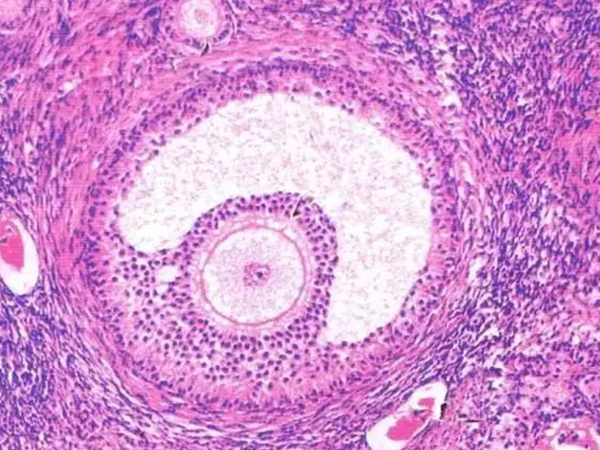

窦状卵泡图片

3、窦状卵泡:这个阶段的卵泡在雌激素和FSH的影响会形成卵泡液,最后融合形成卵泡腔;同时产生芳香化酶,促使雌激素分泌量增加;

特征:此时卵泡的直径可增大至0.2~0.4mm,细胞间产生液体,堆积成腔。